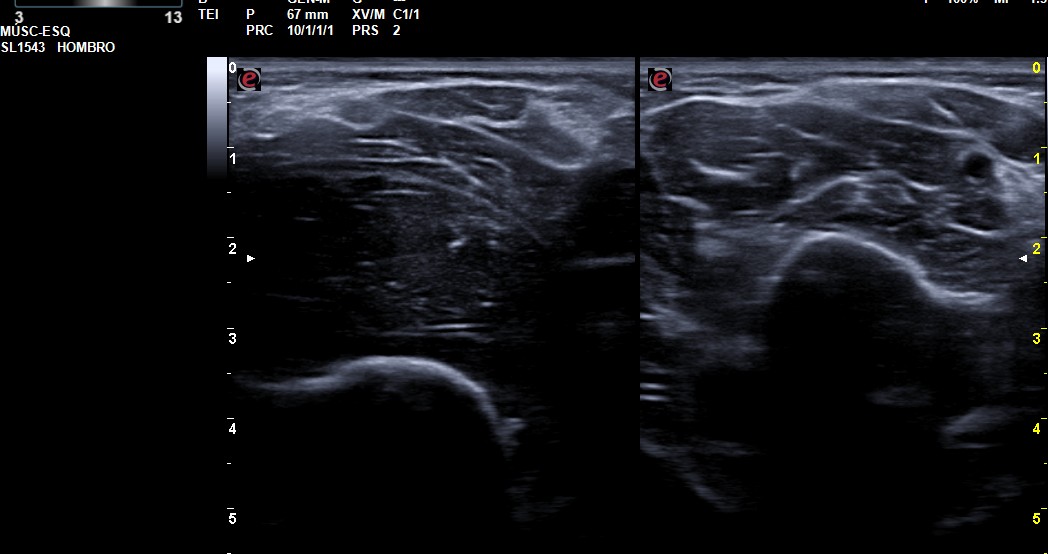

Un varón de 57 años presentaba una masa dura y creciente en codo izquierdo. La ecografía mostró lesión heterogénea y vascularizada. La RMN confirmó lipoma intermuscular gigante, extirpado con éxito.